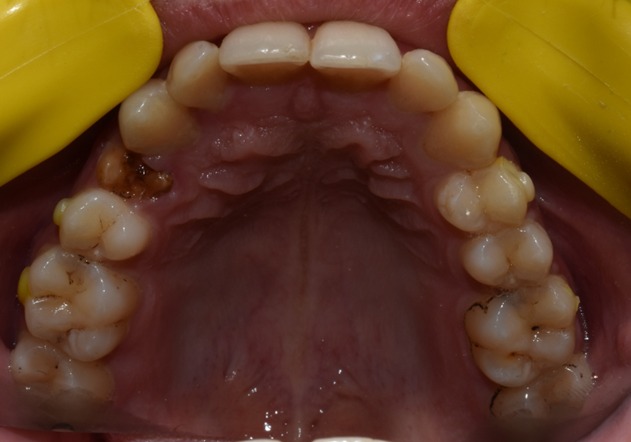

Before & After Results

At Aline Dent, we take pride in delivering visible and lasting improvements in our patients’ smiles. Our before-and-after results highlight the effectiveness of modern dental treatments combined with personalized care. This gallery showcases real dental cases treated at our clinic, giving you a clear idea of how different dental concerns can be corrected with the right treatment approach.

From minor corrections to complete smile enhancements, these teeth transformation results demonstrate how professional dental care can improve both oral health and appearance. Our experienced dental team carefully evaluates each patient’s needs and creates customized treatment plans to achieve natural, healthy, and confident smiles.

In this gallery, you will find a variety of smile makeover cases, including treatments for crooked teeth, gaps, discoloration, damaged teeth, and other common dental concerns.